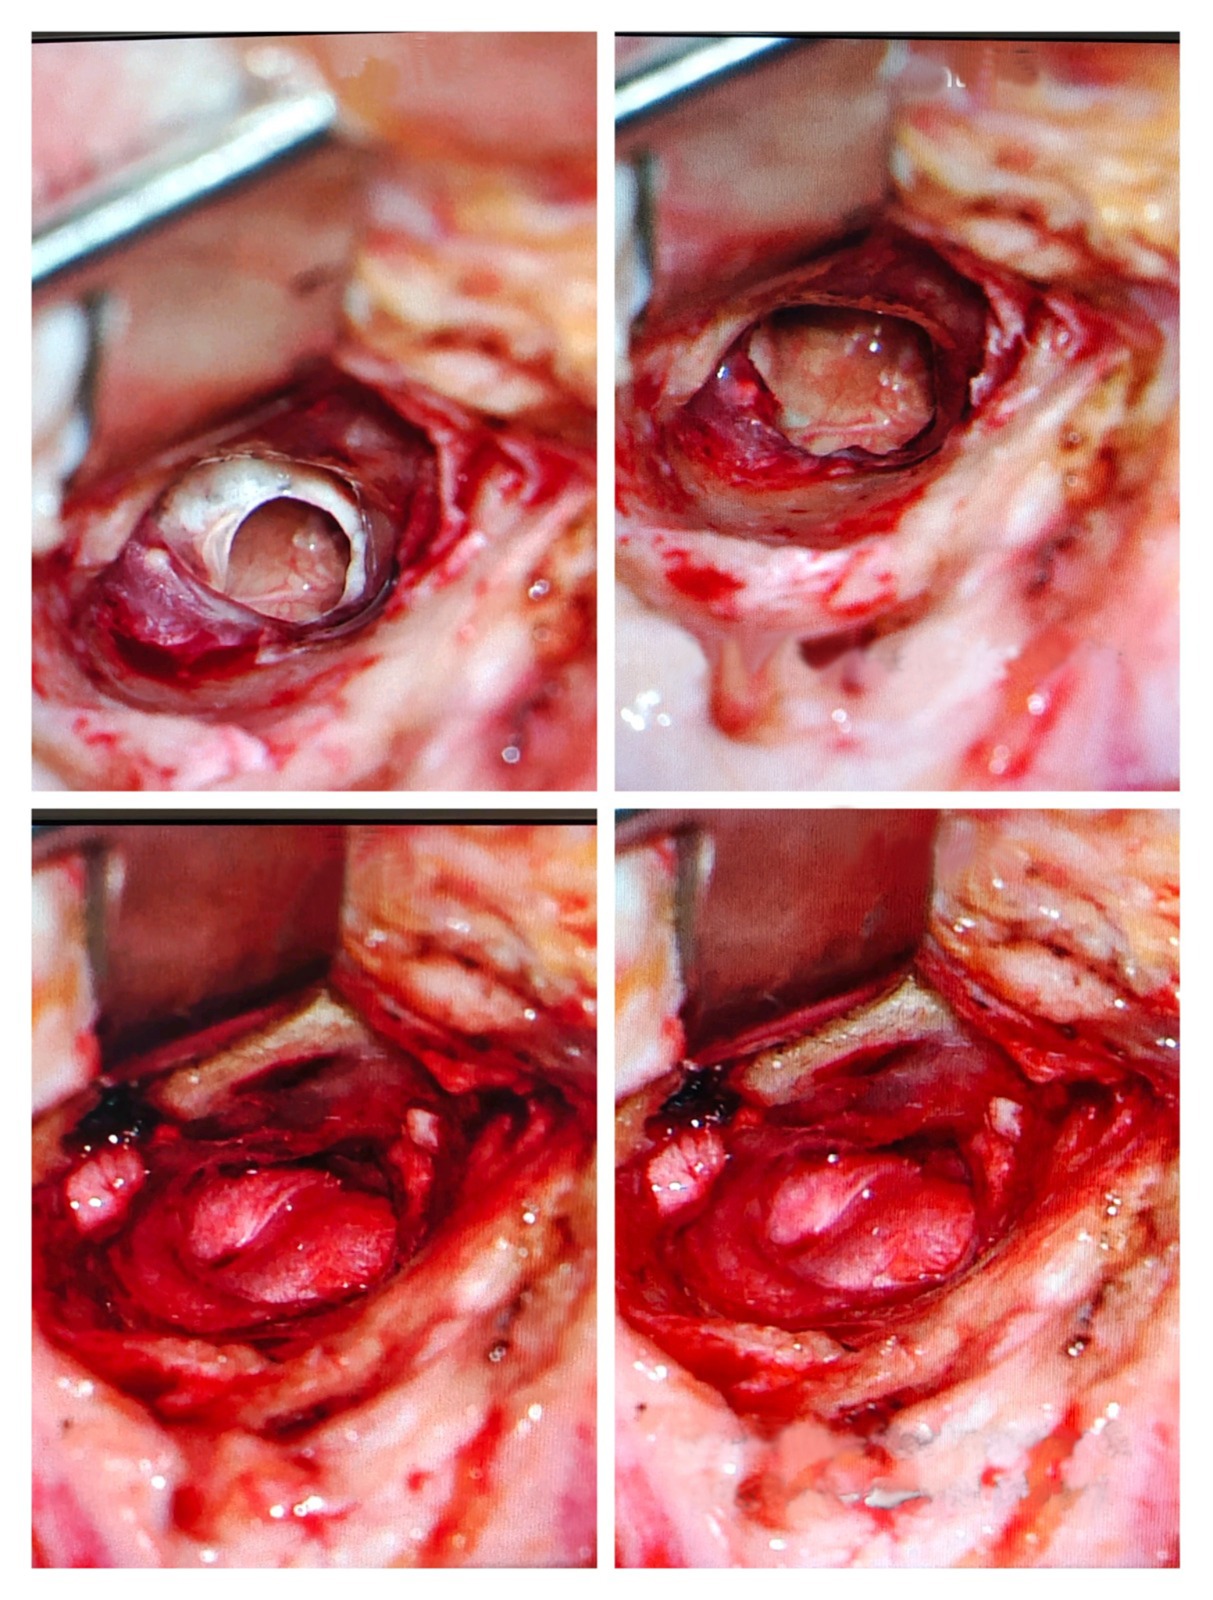

2. Stapedotomy (Otosclerosis Hearing Surgery)

Stapedotomy is performed when the stapes bone becomes fixed due to otosclerosis, causing hearing loss.

Dr. Muddazir replaces the fixed stapes bone with a prosthetic, restoring natural sound conduction.

3. Ossiculoplasty (Middle Ear Bone Reconstruction)

Ossiculoplasty reconstructs or replaces damaged ossicles (hearing bones: malleus, incus, stapes).

4. During the Procedure

- Clear access without large incisions

- Precise handling of microscopic structures

- Minimally invasive techniques